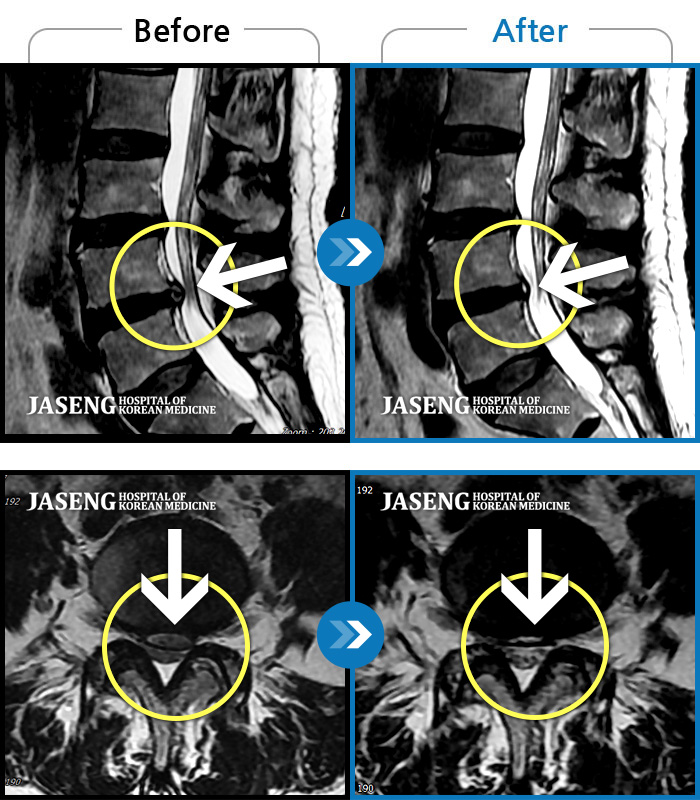

목디스크

도움받은 사례

목동 · 고웅 원장

목통증, 왼쪽 팔저림, 두통, 잇몸통증까지 심해 일상생활 불가

촬영시기

2022.08.20 ~ 2024.02.24

2024.12.24